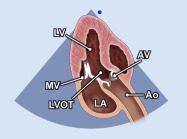

| 2.3. Mặt cắt trục dài cạnh ức phóng đại van động mạch chủ

Cửa sổ siêu âm cạnh ức

Mặt cắt trục dài cạnh ức Đặt hộp phóng đại vào vị trí van động mạch chủ, đường ra thất trái, động mạch chủ lên Chùm siêu âm đặt vuông góc với cấu trúc và có thể đặt đầu dò lên các khoang liên sườn cao hơn nếu cần. |

Van động mạch chủ (AV) | |||||